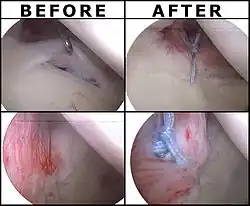

Surgical treatment of SLAP tears has become more common in recent years. The success rate for repairing isolated SLAP tears is reported between 74-94%.[10] While surgery can be performed as a traditional open procedure, an arthroscopic technique[11] is currently favored being less intrusive with low chance of iatrogenic infection.[12]

Following inspection and determination of the extent of injury, the basic labrum repair is as follows.

- The glenoid and labrum are roughened to increase contact surface area and promote re-growth.

- Locations for the bone anchors are selected based on number and severity of tear. A severe tear involving both SLAP and Bankart lesions may require seven anchors. Simple tears may only require one.

- The glenoid is drilled for the anchor implantation.

- Anchors are inserted in the glenoid.

- The suture component of the implant is tied through the labrum and knotted such that the labrum is in tight contact with the glenoid surface.